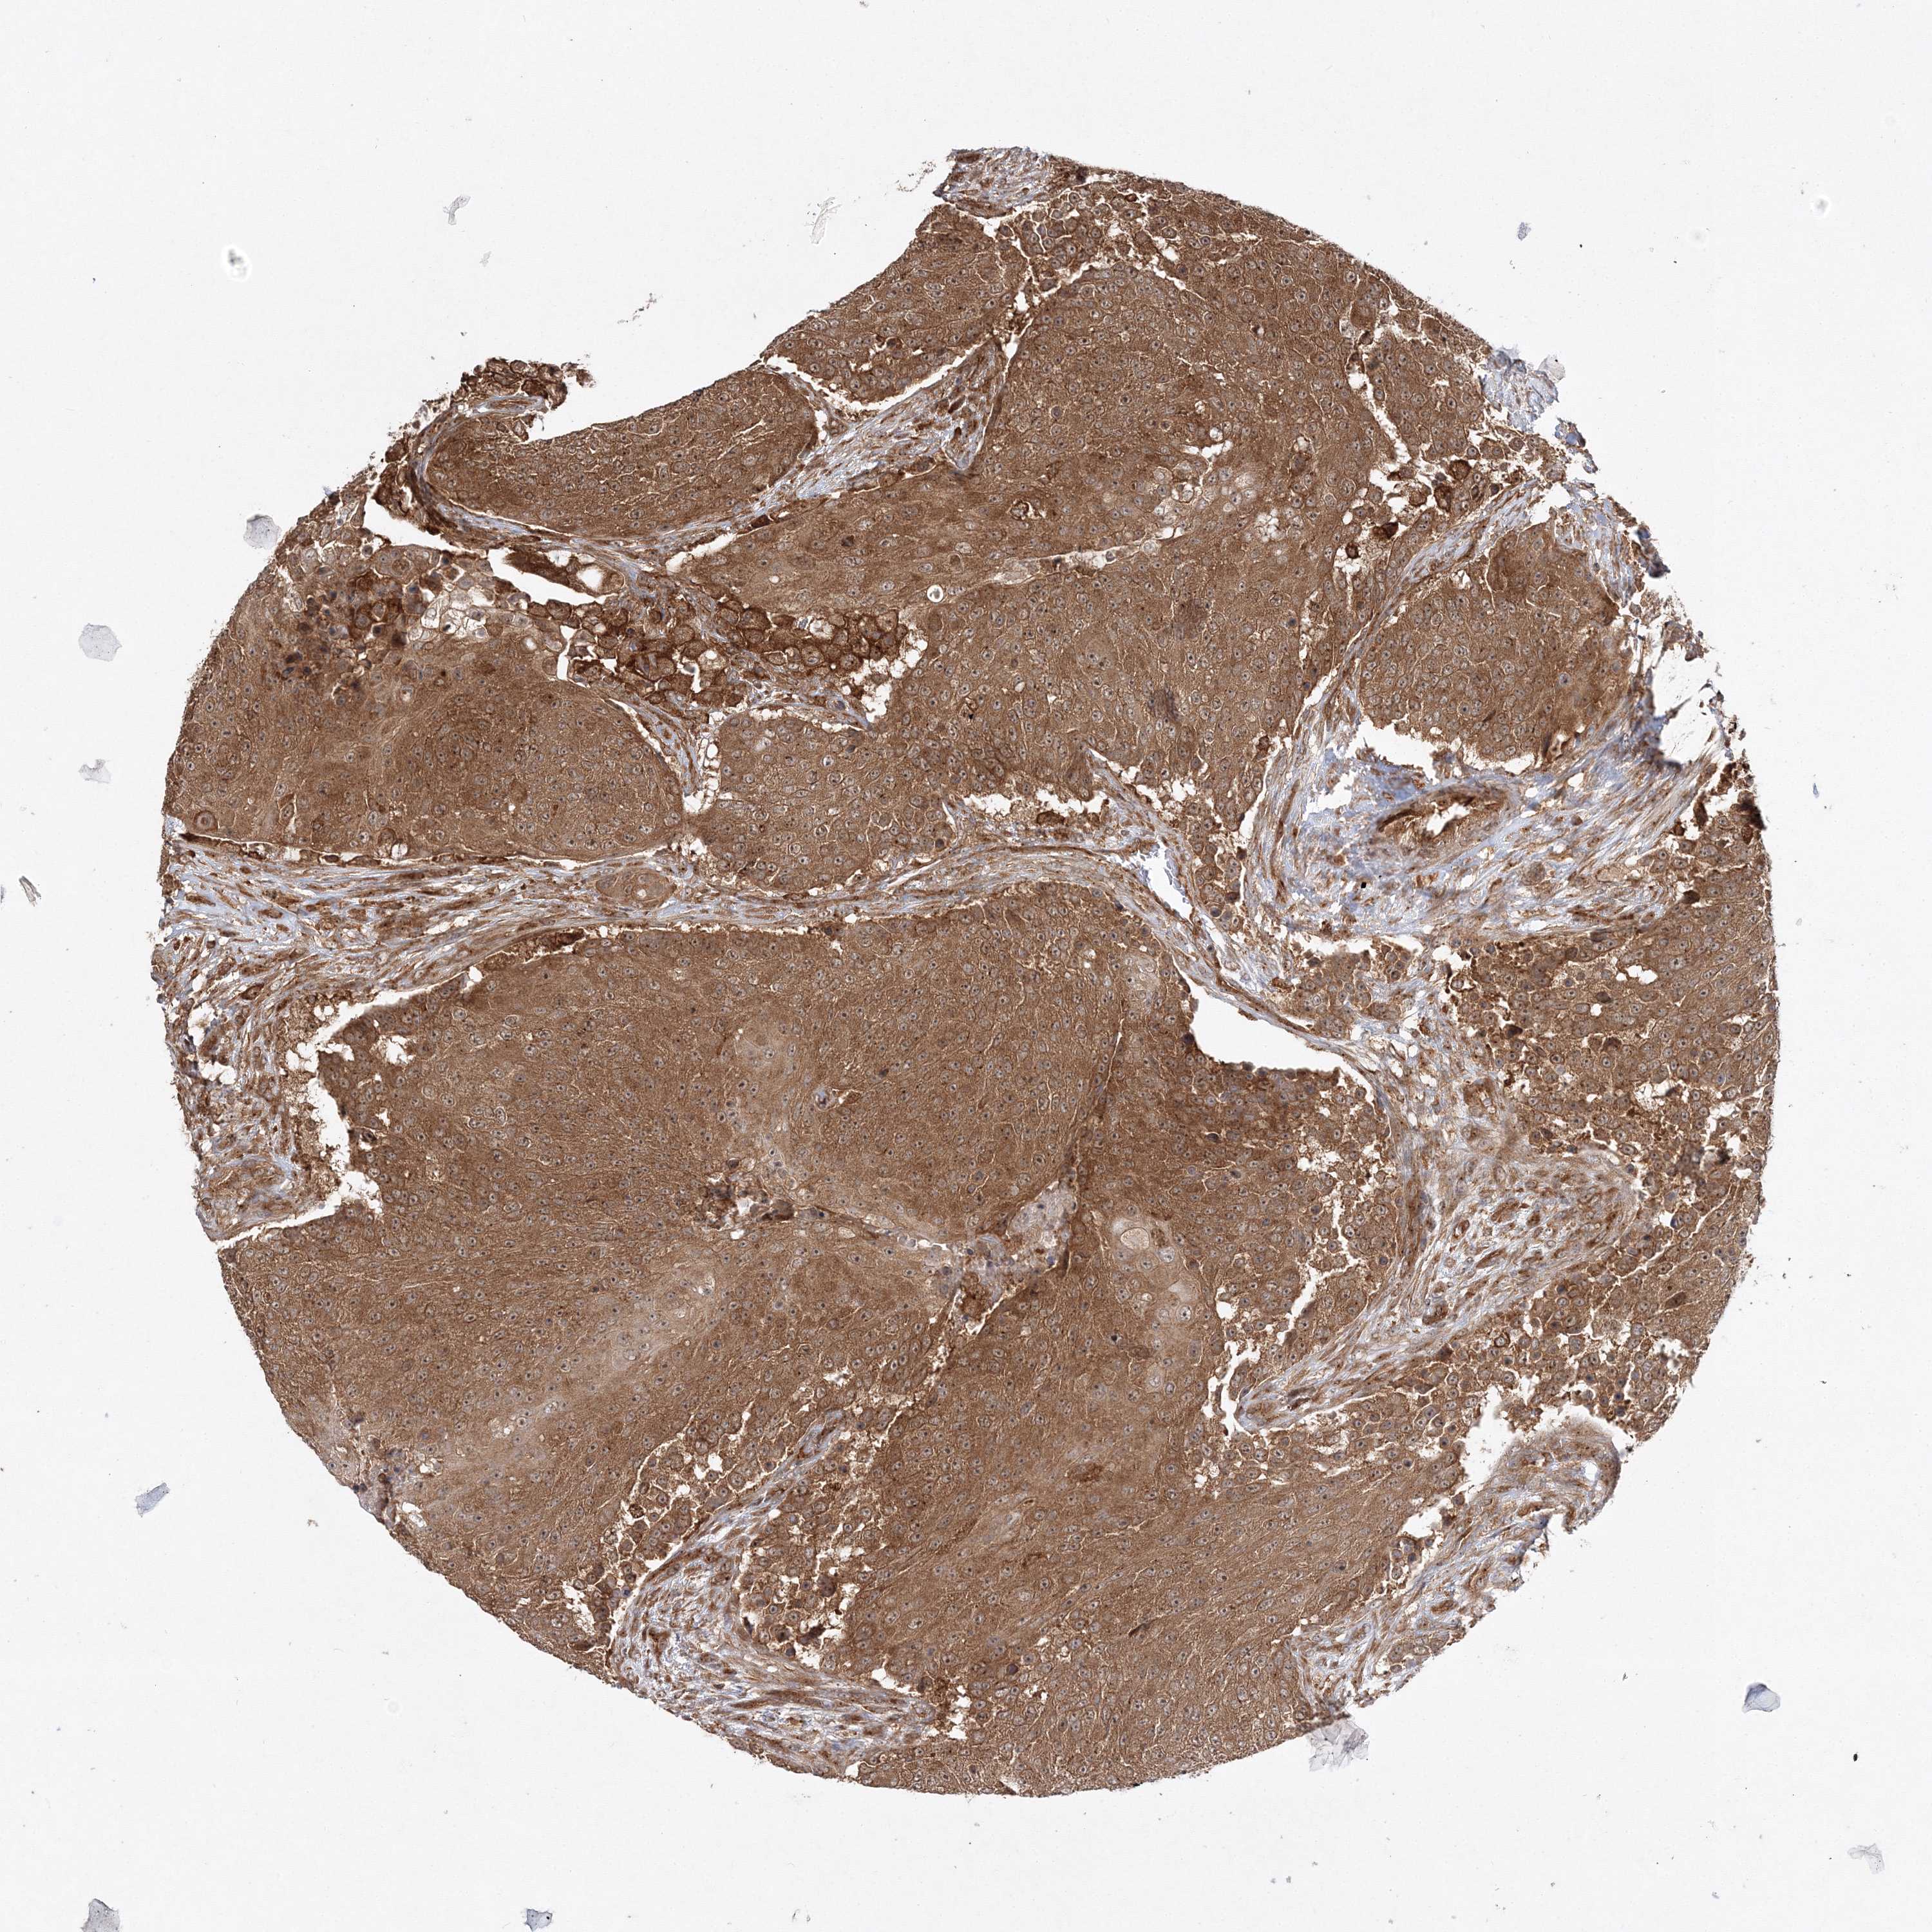

UROTHELIAL CANCER - Protein expressioni

A mouse-over function shows sample information and annotation data. Click on an image to view it in a full screen mode. Samples can be filtered based on level of antibody staining by selecting one or several of the following categories: high, medium, low and not detected. The assay and annotation is described here.

Note that samples used for immunohistochemistry by the Human Protein Atlas do not correspond to samples in the TCGA dataset.

Antibody stainingi

Antibody staining in the annotated cell types in the current human tissue is reported as not detected, low, medium, or high, based on conventional immunohistochemistry profiling in selected tissues. This score is based on the combination of the staining intensity and fraction of stained cells.

Each image is clickable and will lead to virtual microscopy that enables deeper exploration of all samples and also displays staining intensity scores, fraction scores and subcellular localization as well as patient and tissue information for each sample.

Antibody HPA037376

Antibody HPA037565

Staining

High

Medium

Low

Not detected

Intensity

Strong

Moderate

Weak

Negative

Quantity

>75%

75%-25%

<25%

None

Location

Nuclear

Cytoplasmic/membranous

Cytoplasmic/membranous,nuclear

Urothelial carcinoma, Low grade

Urothelial carcinoma, High grade